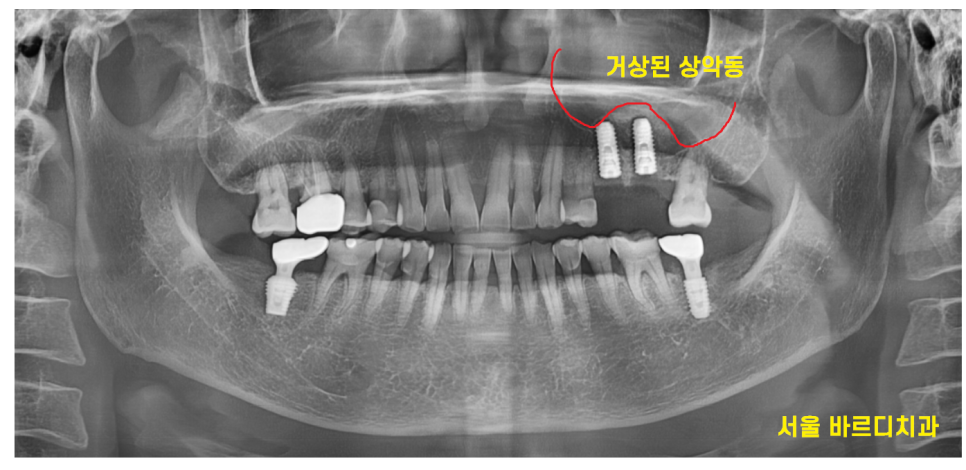

임플란트를 위해 ct 촬영을 시행했습니다.

치아 뿌리 끝과 상악동 구조물이 너무 가깝네요.

2024.02.14

지난 시간에 임플란트를 심기 위해서는

최소 810mm 길이가 필요하다고 말씀드렸죠?

부족한 길이만큼 상악동을 들어 올려

뼈 이식 후 임플란트를 해야겠네요.

진단 결과 남아있는 뼈의 두께도 얇고

치아 뼈 폭도 좁아서 Lateral 방법으로 진행하기로 상담 드렸습니다.

수술 후 사진입니다.

상악동을 올리면서 뼈이식을 진행하여

돔 형태로 잘 만들어진 것이 확인됩니다.